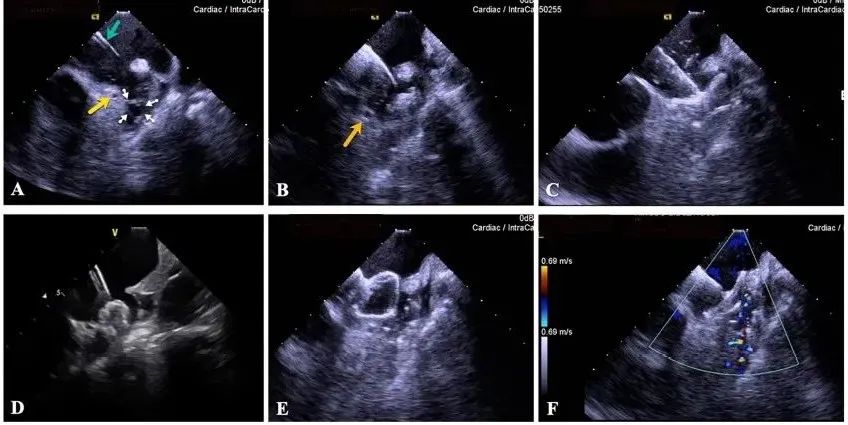

一種與心導(dǎo)管檢查相結(jié)合的超聲心動(dòng)圖診斷新興技術(shù),通過將超聲探頭置于心腔內(nèi)部,發(fā)射并接收超聲信號(hào),來精確獲取心臟解剖結(jié)構(gòu)、心臟血流動(dòng)力學(xué)等信息的實(shí)時(shí)成像。與其他影像技術(shù)相比,ICE技術(shù)具有操作簡單、無輻射、安全性高、手術(shù)效率高、實(shí)用等優(yōu)勢,ICE在很大程度上有望取代經(jīng)食道超聲心動(dòng)圖(TEE),成為電生理和結(jié)構(gòu)性心臟病領(lǐng)域的理想成像方式。

目前ICE技術(shù)已被應(yīng)用于左心耳封堵、房顫射頻消融、二尖瓣成形、房間隔缺損封堵等多種心臟介入手術(shù),應(yīng)用場景主要圍繞心臟電生理、結(jié)構(gòu)性心臟病等領(lǐng)域,目前以電生理應(yīng)用為主。數(shù)據(jù)顯示,我國結(jié)構(gòu)性心臟病介入器械市場規(guī)模已從2017年的4億元增長至2021年的20億元,年復(fù)合增長率達(dá)48.3%;預(yù)計(jì)到2025年,該市場規(guī)模將達(dá)到104億元,可以預(yù)見ICE市場規(guī)模也將同步高速增長,未來市場發(fā)展空間廣闊。

心腔內(nèi)超聲(ICE)技術(shù)壁壘極高,國內(nèi)主要廠商核心部件仍舊為進(jìn)口,集成了超聲和圖像處理最前端技術(shù),包括超聲探頭、線纜、軟件成像算法等,是當(dāng)前內(nèi)窺超聲方向最具挑戰(zhàn)的領(lǐng)域。ICE的應(yīng)用經(jīng)歷了2D平面成像、3D三維立體成像、以及4D的實(shí)時(shí)三維立體成像階段。